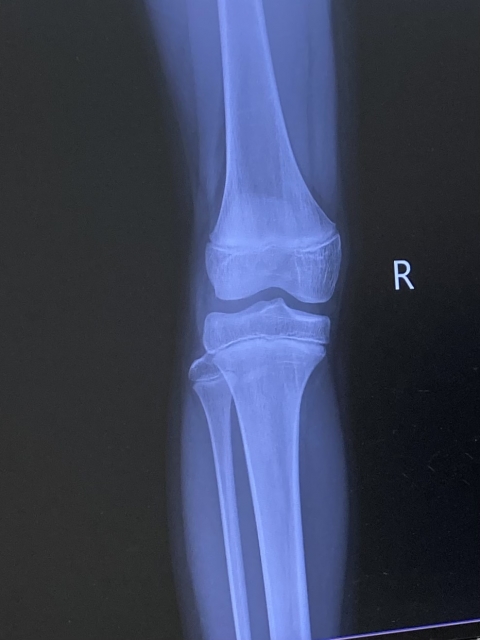

【変形性膝関節症(膝の痛み)】

変形性膝関節症とは?

変形性膝関節症とは、膝の関節のクッションである軟骨がすり減り、炎症や変形が起こることで痛みが出る状態です。

特に中高年の方に多く、日常生活の中で徐々に症状が進行していくのが特徴です。

但し、変形性膝関節症は、加齢だけが原因ではありません

膝の使い方・姿勢・筋力低下・生活習慣が大きく関係しているため、適切な検査評価と治療方法が重要です。